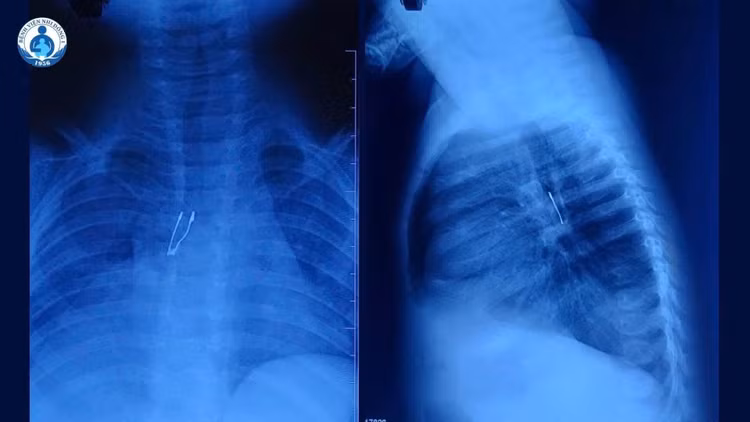

Kết quả X-quang cho thấy dị vật cản quang nằm ở phế quản gốc phải, kèm theo dấu hiệu xẹp phổi phải không hoàn toàn và tràn khí trung thất – những biến chứng báo hiệu tình trạng không đơn giản.

Kết quả X-quang cho thấy dị vật cản quang nằm ở phế quản gốc phải - Ảnh BVCC